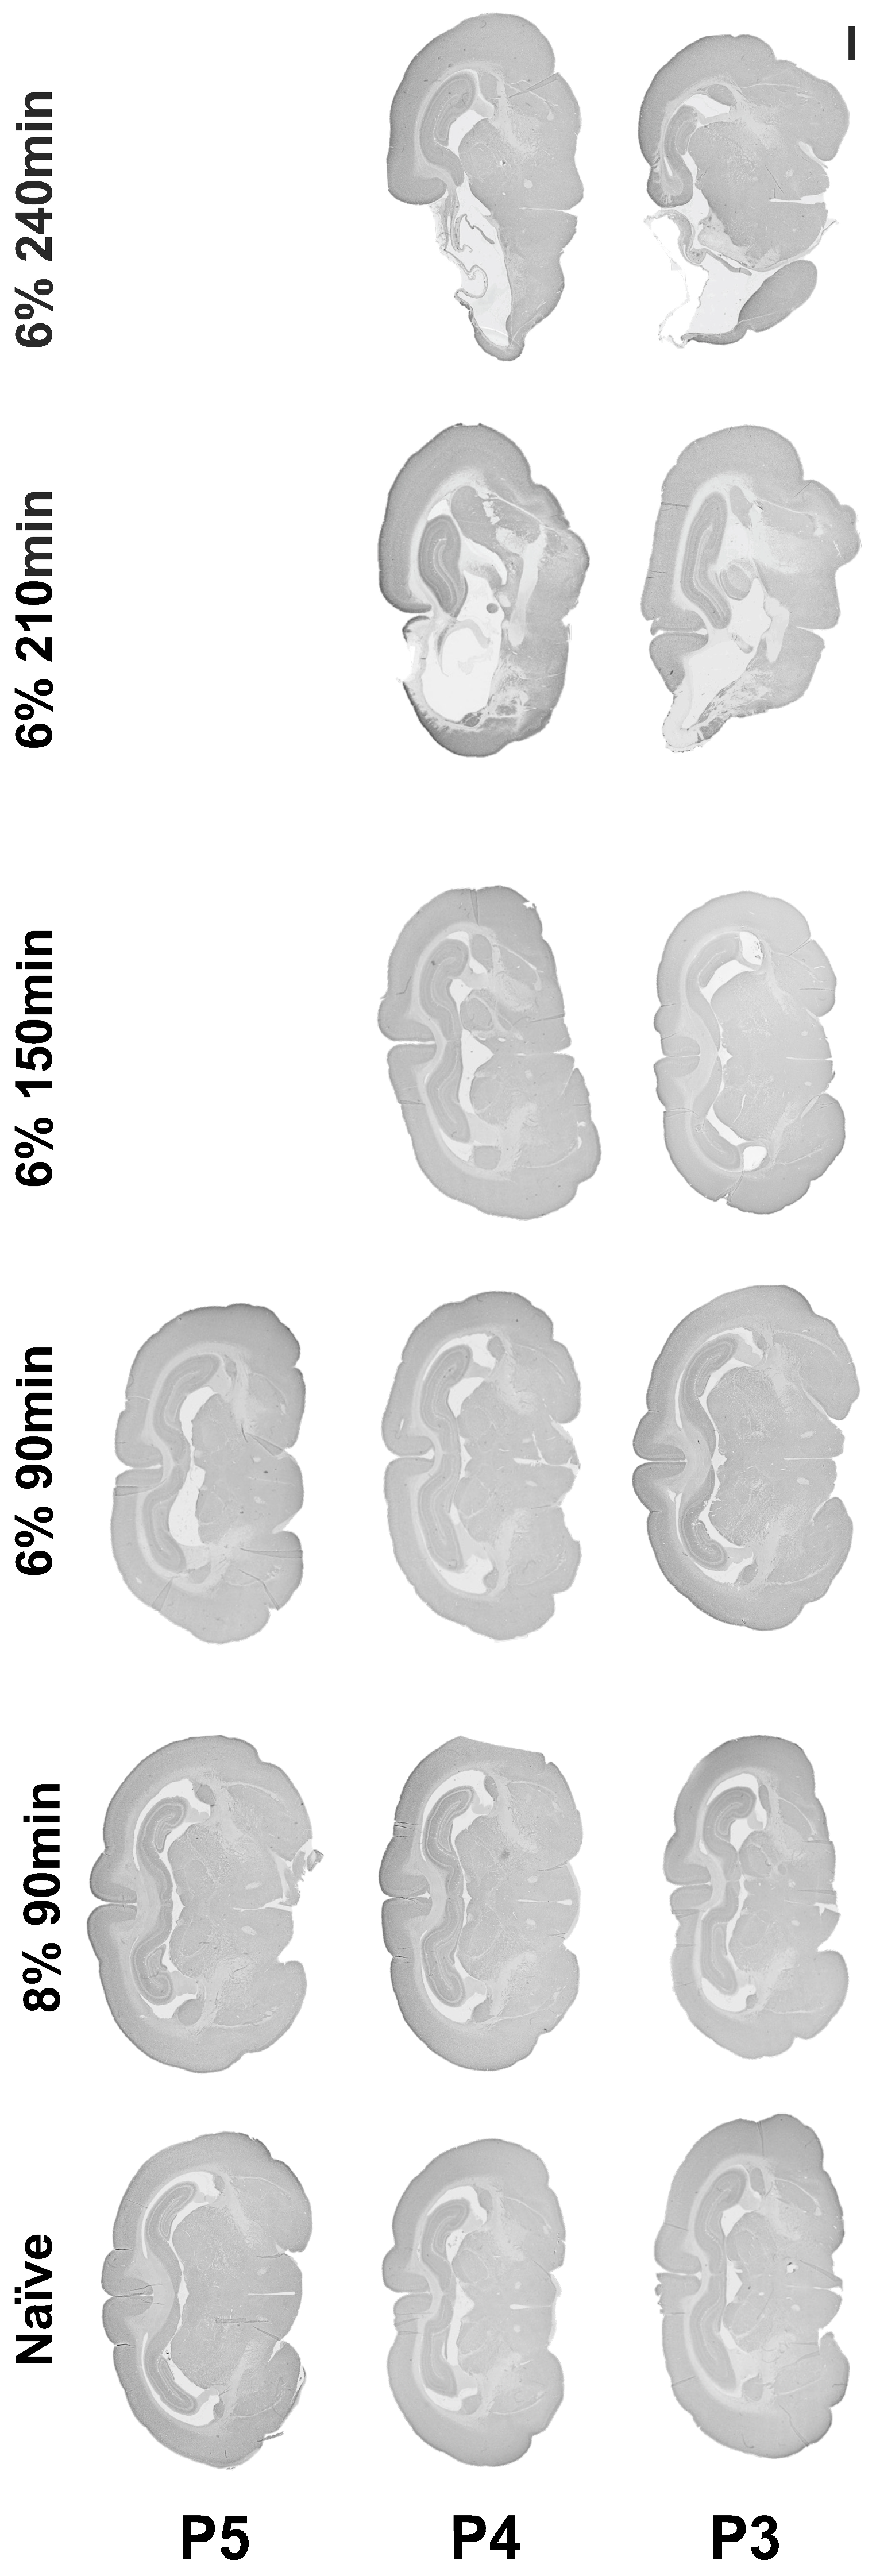

Following permanent ligation of the left common carotid artery, oxygen reduction to 8% or 6% for a duration of 90 min did not result in hypoxic–ischemic brain injury at P3, P4, or P5. Oxygen reduction to 6% in both the P3 and P4 animals, with increasing hypoxia duration gradually up to 240 min, resulted in ipsilateral brain injury after exposure for 210 min and 240 min to 6% hypoxia (Figure 2).

Figure 2.

Establishing a rabbit model of hypoxia-ischemia. Micrograph representation of brain injury following hypoxia-ischemia performed between P3 and P5, with gradual reduction in oxygen from 8 to 6% and gradual increase in hypoxia duration from 90 min to 240 min. Scale bar = 2 mm.